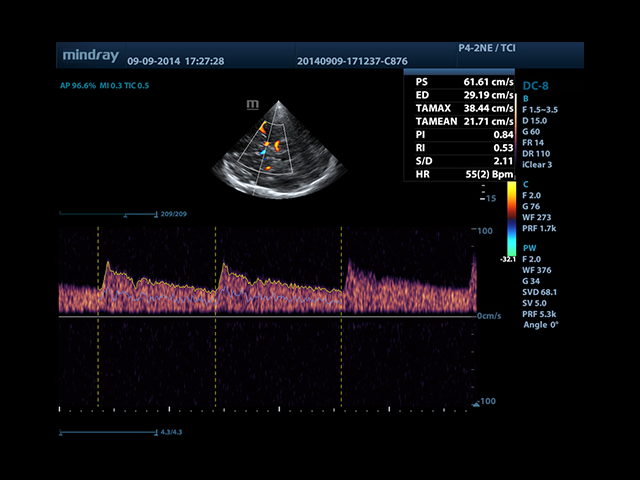

Mindray DC-8 Exp – это ультразвуковой аппарат с архитектурой mQuadro и функцией эластографии Natural Touch. Он оснащен высококлассным 21-дюймовым TFT-монитором с разрешением Full HD. Данный аппарат представляет интерес для специалистов, занимающихся обследованием мягких тканей с использованием эластографии. Режим объемного 4D-сканирования позволяет получать максимально точные диагнозы, сокращая количество неэффективных процедур.

Mindray DC-8 Exp оснащен новым поколением датчиков с увеличенным количеством элементов и инновационной технологией "3T". Это позволяет достичь высокой детализации и качества изображения. Благодаря новейшей технологии iFlow, можно визуализировать даже самые мелкие сосуды и кровеносные пути.

Сверхширокополосная нелинейная обработка изображений снижает визуальные шумы на 30% по сравнению с другими системами. Технология iClear позволяет устранить зернистость изображения, а iBeam (технология пространственного компаундинга) обеспечивает высокое качество сканирования органов и тканей под различными углами.

• Smart Doppler - автоматическая подстройка расположения рамки цветового доплера и контрольного объема импульсно-волнового доплера нажатием кнопки.